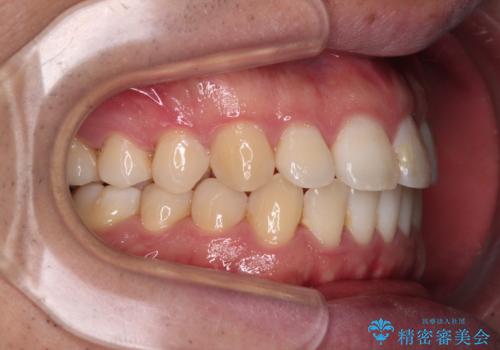

インビザラインで奥歯の咬み合わせと前歯のデコボコを改善

- 前歯のデコボコと奥歯の咬み合わせを気にして来院された患者様です。

前歯のデコボコはインビザラインで十分に対応可能と判断できましたが、咬合力が強いため、臼歯(特に右側)の交叉咬合はインビザライン単体では困難と思われました。

まずはインビザライン単体で矯正治療を開始し、交叉咬合が改善されない場合にはアンカースクリューなどの使用を検討することとしました。

インビザライン単体では右側の交叉咬合を解消することができなかったため、アンカースクリューを併用して咬合を改善させました。